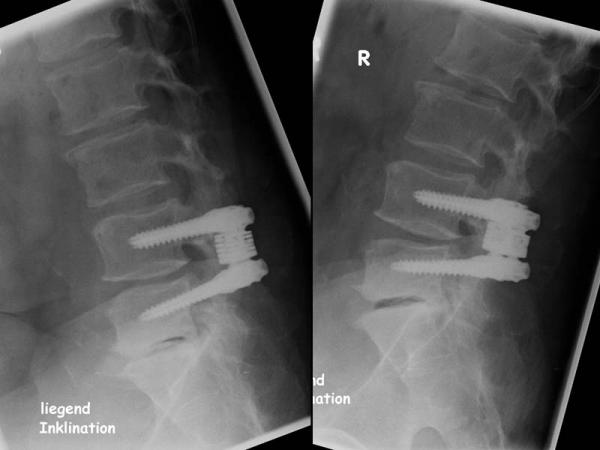

The dynamic stabilisation system (DSS) of the company Paradigm, complements the possibilities in the surgical treatment of degenerative spine disease. It is a on pedicle screws designed system that is based on modules and makes the combination of DSS dynamic couplers with DSS fusion couplers on adjacent heights possible. Thus, with the same system a segment can show a functionally dynamic stabilisation (non-fusion without acampsia) while the adjacent segment has a rigid segmental fixation (fusion, acampsia). The DSS-dynamic-coupler increases the acampsia of the affected motion segment and limits the extent of motion in flexion, extension, lateral flexion and rotation with preserved mobility. By choosing the appropriate size of the DSS-dynamic-coupler, the height of the posterior segment can be adjusted as well. The DSS Fusion coupler provides a rigid segmental fixation, using the same instruments. One of the special characteristics and advantages of the system is the use of percutaneous screw positioning, which favours a minimally invasive, muscle-considering procedure.

Strictly speaking, the system was designed to control the “Active Zone” movements, which are usually associated with pathological and painful movement arcs. The first implantations showed a very good success with the patient. The system can also be used in addition to a decompression surgery if on preoperative radiographs, signs of instability appear.